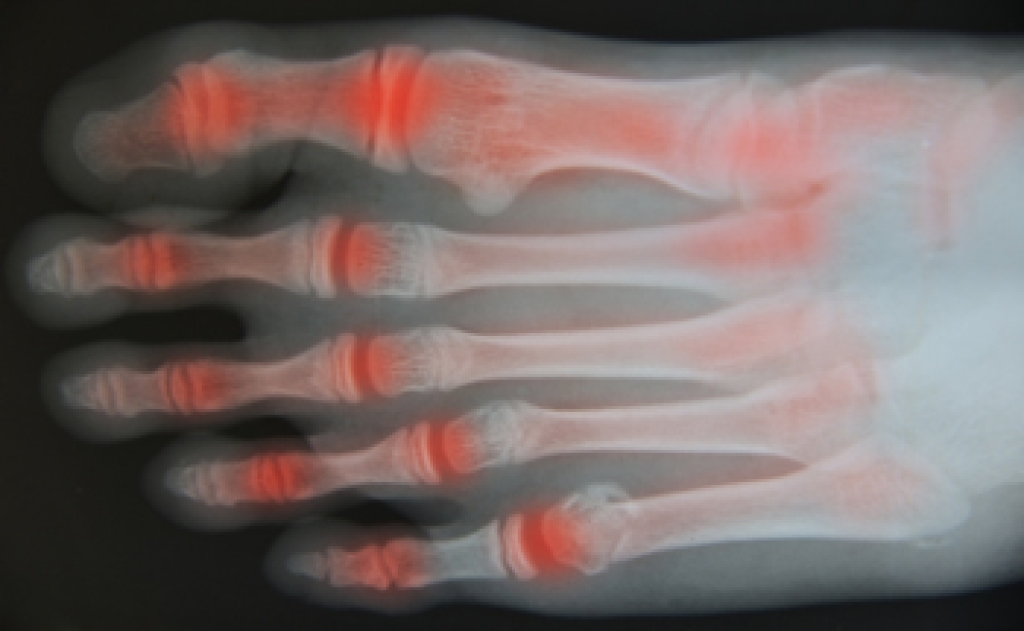

Rheumatoid Arthritis (RA) is an autoimmune disorder in which the body’s own immune system attacks the membranes surrounding the joints. Inflammation of the lining and eventually the destruction of the joint’s cartilage and bone occur, causing severe pain and immobility.

Although RA usually attacks multiple bones and joints throughout the entire body, almost 90 percent of cases result in pain in the foot or ankle area.

- Swelling and pain in the feet

- Stiffness in the feet

- Pain on the ball or sole of feet

- Joint shift and deformation